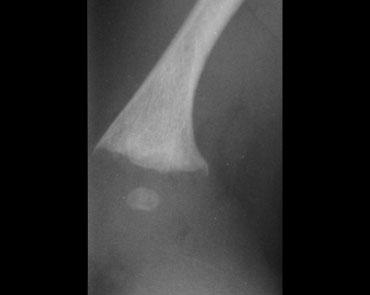

Gãy xương góc (Corner fracture)

Gãy xương góc hành xương, còn được Kleinman gọi là tổn thương hành xương kinh điển, lần đầu tiên được mô tả bởi Caffey, người đã ghi nhận những gãy xương đặc biệt này ở trẻ em có tụ máu dưới màng cứng. Chúng thường xuất hiện hai bên và ở đầu dưới xương chày, thường gặp hơn ở phía trong.

Khi một mảnh xương nhỏ bị bong ra do lực cắt tác động lên sụn tăng trưởng mỏng manh, nó được nhìn thấy như hình ảnh gãy xương góc điển hình. Những gãy xương này phổ biến nhất ở xương chày, đầu dưới xương đùi và đầu trên xương cánh tay. Chúng thường xuất hiện hai bên.

Những gãy xương này thường rất kín đáo, và khả năng phát hiện phụ thuộc trực tiếp vào chất lượng của các nghiên cứu hình ảnh.

Chính vì lý do này, khảo sát xương toàn thân trong các trường hợp nghi ngờ lạm dụng trẻ em phải được thực hiện với sự chú ý tối đa đến chất lượng phim chụp.